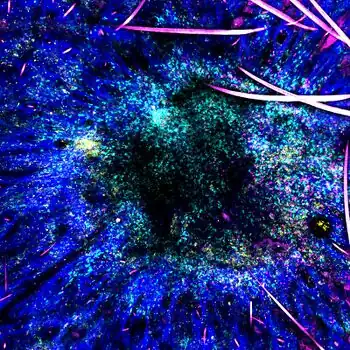

Staphylococcus epidermidis bacteria green in the extracellular matrix

Staphylococcus epidermidis bacteria green in the extracellular matrix Staphylococcus epidermidis biofilm on titanium substrate

The ability to form biofilms on plastic devices is a major virulence factor for S. epidermidis. One probable cause is surface proteins that bind blood and extracellular matrix proteins. It produces an extracellular material known as polysaccharide intercellular adhesin (PIA), which is made up of sulfated polysaccharides. It allows other bacteria to bind to the already existing biofilm, creating a multilayer biofilm. Such biofilms decrease the metabolic activity of bacteria within them. This decreased metabolism, in combination with impaired diffusion of antibiotics, makes it difficult for antibiotics to effectively clear this type of infection.[5] S. epidermidis strains are often resistant to antibiotics, including rifamycin, fluoroquinolones, gentamicin, tetracycline, clindamycin, and sulfonamides.[11] Methicillin resistance is particularly widespread, with 75-90% of hospital isolates resistance to methicillin.[11] Resistant organisms are most commonly found in the intestine, but organisms living freely on the skin can also become resistant due to routine exposure to antibiotics secreted in sweat.

Moreover, S. epidermidis biofilm formation by releasing the exopolysaccharide intercellular adhesion (PIA) provides the susceptible anaerobic environment to P. acnes colonisation and protects it from the innate human immunity molecules.[15]